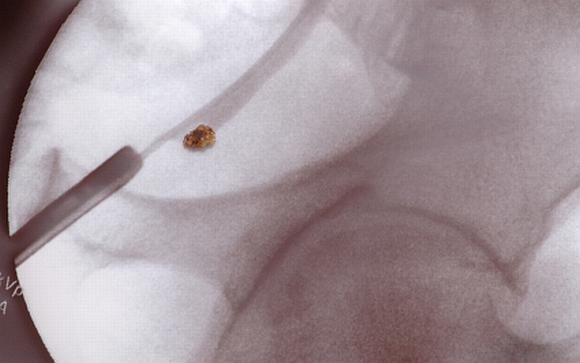

A vesekő tünetei és kezelése

Gyakori betegség, minden tizedik embert érint valamikor élete során a vesekő. A legmagasabb az arány az Egyesült Államokban, ahol az elmúlt két-három évtizedben folyamatosan emelkedett az érintettek száma. Mik a tünetei és hogyan kezelhető? Kiderül cikkünkből.

A vesekövek ásványi sóból képződött kicsi és kemény lerakódások a vese belsejében. Amikor a vizelet túl koncentrált, az már egy jele lehet a későbbi vesekőképződésnek. Először kristályok képződnek, amelyek idővel nagyobb kővé érnek össze.

Elegendő folyadék fogyasztásával azonban sokat lehet tenni a megelőzésért. Eltávolításának módja a kő méretétől függ. Ha kisebb, akkor jó eséllyel spontán módon eltávolodik. Sok víz fogyasztása és fájdalomcsillapító szerek szedése segíthet ebben. Nagyobb kövek esetén azonban invazív beavatkozásokra lehet szükség. A műtét során a húgycsövön keresztül vezetnek fel egy csövet, amely szétzúzza a nagyobb köveket kisebb darabokra, amelyek könnyebben eltávolodnak a szervezetből.